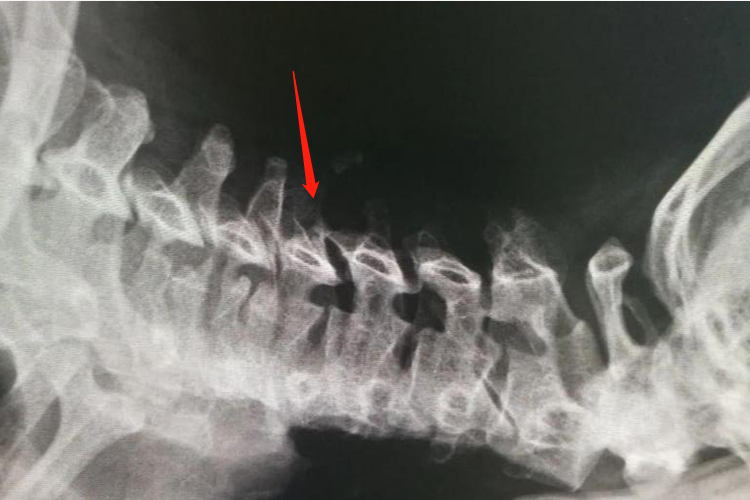

神经根型颈椎病:患者以颈部疼痛、上肢麻木、感觉减弱为主要症状,早期出现腱反射活跃,后期反射逐渐减弱,严重者反射消失。X线片检查多可显示颈椎曲度变直,椎间孔狭窄;颈椎MRI提示椎间盘突出,突出的椎间盘进入神经根管。